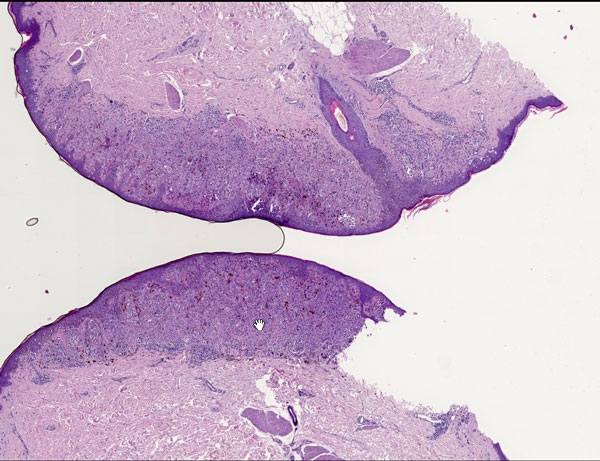

Digitale PAthologie: Melanom Mit freundlicher Genehmigung von PreciPoint GmbH www.precipoint.de Klicken Sie auf das Bild, um zu zoomen